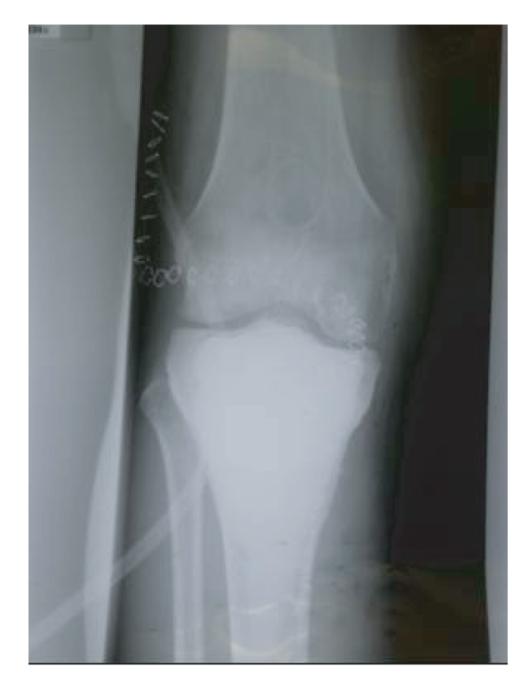

Bone cement reaches significant temperatures and is known to cause thermal and chemical damage to various tissues. All the reports of such damage occurred following a direct contact of the tissue or structure with cement. We report the case of a patient with a giant cell tumour of the proximal tibia who underwent curettage and bone cement application through a posterior approach and subsequently developed full thickness pretibial skin damage despite showing no evidence of any direct contact of the involved skin with bone cement. This is the first report of its kind and though anecdotal is a serious complication that surgeons should be aware of.